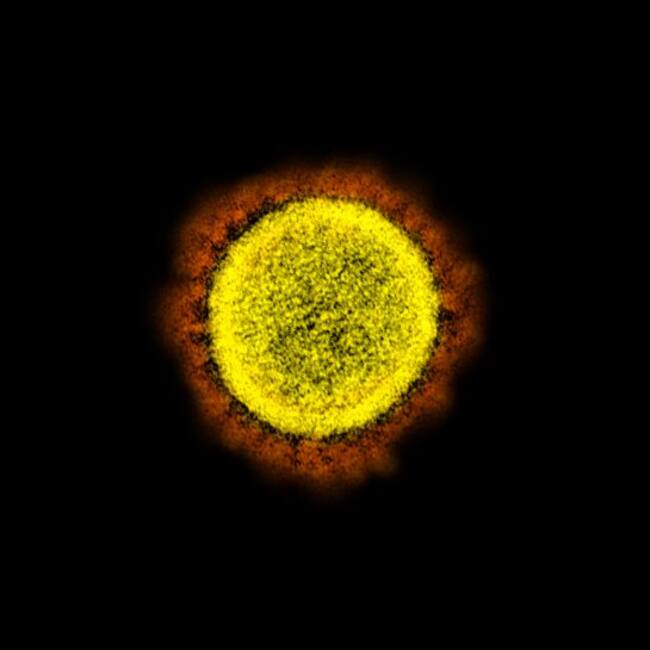

Captan al nuevo coronavirus dañando las células humanas

Fotos tomadas con microscopio electrónico captan cómo el coronavirus ataca las células humanas con en proceso de autodestrucción, rodeadas por los mic

Fotografías del nuevo coronoavirus SARS-CoV-2 que ha causado la pandemia en este 2020 se han difundido por el Instituto Nacional de Alergias y Enfermedades Infecciosas de Estados Unidos a los que tuvimos acceso.

Es una serie de fotografías tomadas por un microscopio electrónico para estudiar y observar la forma en que ataca las células del cuerpo humano, en estas imágenes se puede ver cómo los virus rodean las células sanas y se adhieren para pasar al proceso de apoptosis, que es la destrucción celular provocada por el mismo organismo para controlar su desarrollo o crecimiento.

Una de las características del virus es la corona (de ahí el nombre de coronavirus) y que con esas ‘espinas’ de proteína, se adhiere a la célula sana y obliga a replicar el ARN que contiene su información genética como si fuera propio. Este virus es tan pequeño que no se alcanza a observar completamente en el lente tradicional, alcanza cerca de los 100 nanómetros.

Las fotografías fueron tomadas y después coloreadas al publicarlas.